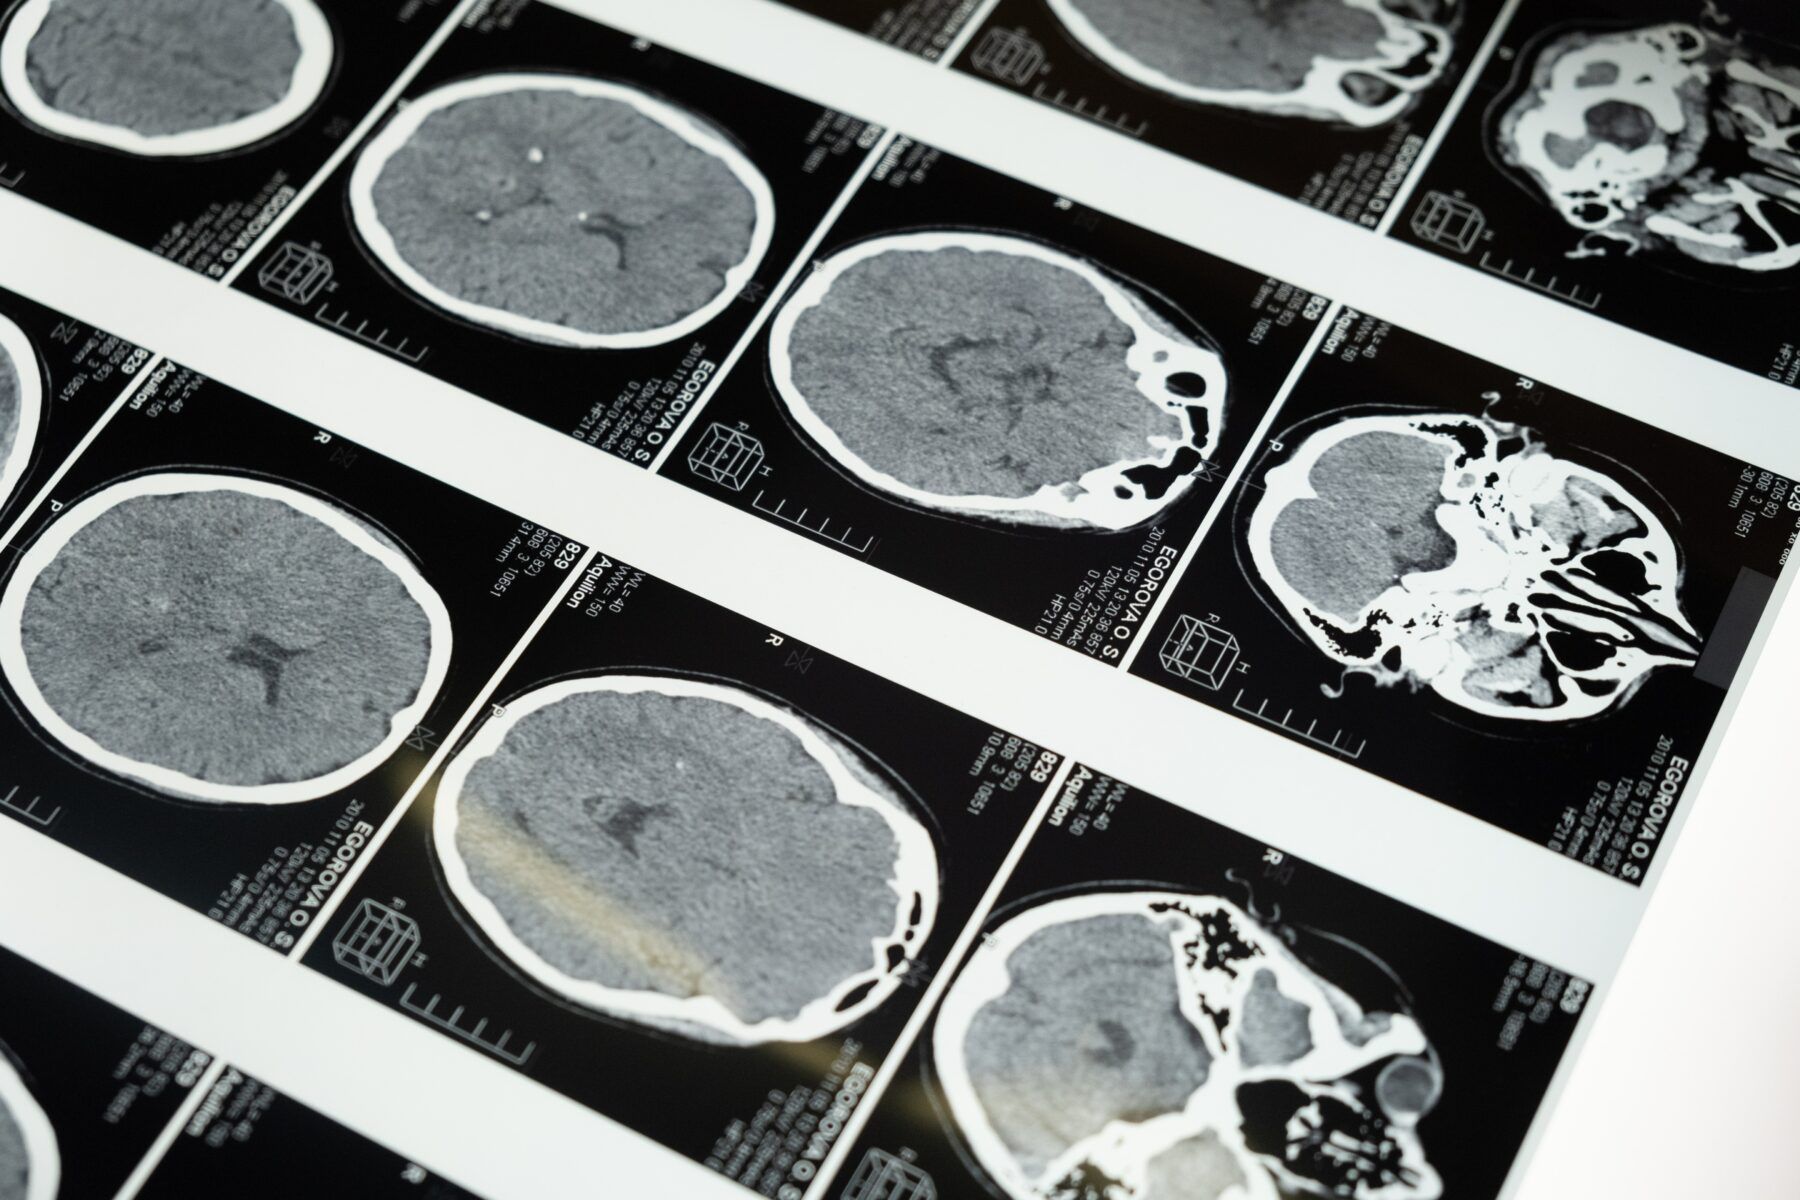

Стартап Ілона Маска Neuralink, який досліджував та виготовляв мозкові чіпи, проводив багаторічні випробування в державному університеті Каліфорнії у Девісі. Метою досліджень була розробка мозкових імплантів, які б взаємодіяли з електронними пристроями.

Стало відомо, що через витікання токсичного клею з імпланту, що розробила компанія Neuralink, у піддослідної мавпи буквально розірвався мозок.

За результатами розтину виявилося, що всередині черепа тварини сильно зріс тиск, через що її мозок деформувався та розірвався. Причиною став токсичний клей самого чіпа, який був прикріплений до черепа тварини.

Через витік клею з’явилося запалення, що спричинило тиск на спинномозкову рідину.